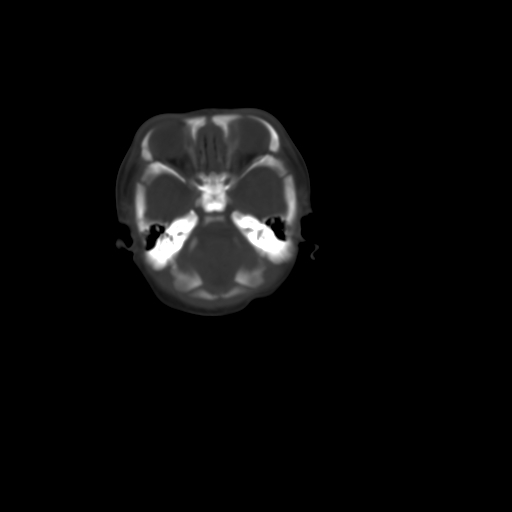

男,12天,自然分娩,其母发现右顶部头皮包块逐渐增大。

右顶部头皮血肿

右顶部头颅血肿(骨膜下血肿)

右顶骨呈膨胀性改变,骨纤维结构不良?

右顶部头皮血肿,可能是产道挤压所致。以后会慢慢恢复。

鉴别:骨膜下血肿,一般为产伤,应用产钳之类的吧

疑问:患儿脑白质密度比较低,基底节区密度比较高,类似于“双圈征”脑沟密度也偏高。该婴儿可有别的异常吗?反射正常吗?评分能达到5分吗?如果正常,就随诊观察吧。不正常要考虑到缺血缺氧性脑病。